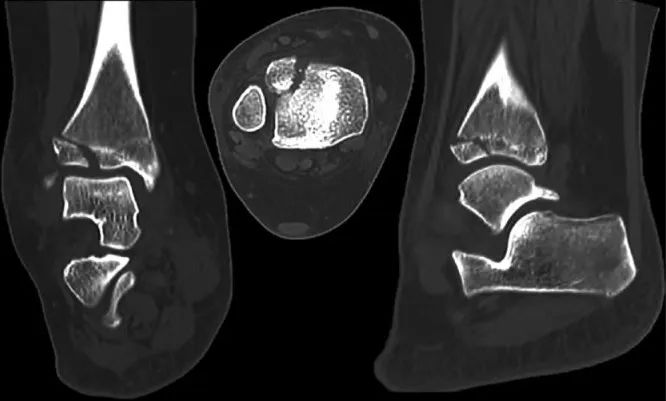

图源:DOI: 10.1302/2058-5241.6.200042.